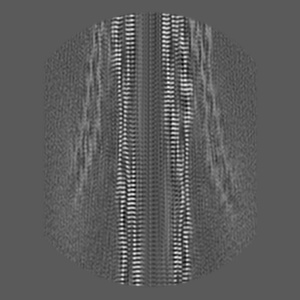

In vitro assembled 266/297 - 391 tau filaments with MgCl2 and NaCl (14b)

EMD-14044

Helical reconstruction

3.26 Å

Sample Organism: Homo sapiens

Sample: Tau

Fitted models: 7qkj

Deposition Authors: Lovestam S, Scheres SHW

Assembly of recombinant tau into filaments identical to those of Alzheimer's disease and chronic traumatic encephalopathy.

Lovestam S, Koh FA, van Knippenberg B , Kotecha A , Murzin AG, Goedert M , Scheres SHW

(2022) eLife , 11

PUBMED: 35244536

DOI: doi:10.7554/eLife.76494